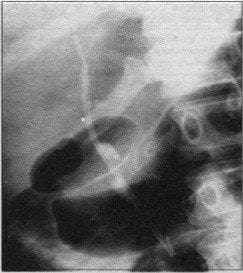

A un porcentaje importante de enfermos se les hizo la colangiografía directamente con el esfinterótomo, evitando así el cambio de cánula diagnóstica a esfinterótomo y procediendo inmediatamente a la esfinterotomía; así mismo, si la colangiografía no mostraba cálculos, se efectuaba en un número importante de pacientes una pequeña esfinterotomía y acto seguido, se introducía una canastilla de Dormia para explorar directamente la vía biliar intra y extrahepática en busca de cálculos; en los casos donde se diagnosticó coledocolitiasis, se procedió al retiro de aquellos mediante el uso de canastilla de Dormia (Figs. 1 y 2). Cuando el paciente presentaba coledocolitiasis y colelitiasis, se efectuaba la extracción endoscópica de los cálculos del colédoco y al día siguiente era llevado a colecistectomía laparoscópica.

Fig. 1. La colangiografía endoscópica muestra un cálculo único distal.

Fig. 2. El mismo paciente de la Fig. J. Visión endoscópica del cálculo atrapado en la canastilla del Dormia, ya extraído de la vesícula biliar.